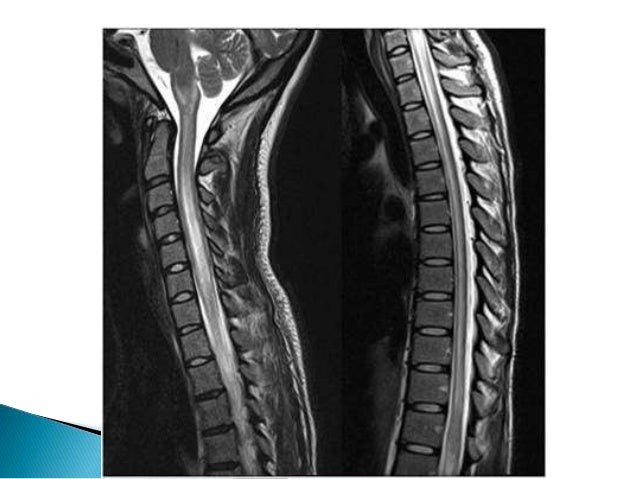

13. 13.  Represent extensive involvement of the spinal cord, with abnormal T2 signal traversing at least three vertebral body segments in length.  Differential diagnosis  NMO(typical)  Multiple sclerosis- confluent short segment lesions mimicking LESC  Immunological- Neurosarcoidosis,Sjogrens,SLE  Behcet’s disease  Paraneoplastic myelitis  Post infectious  Vascular- Infarction,Dural AV fistula  Metabolic and radiation myelopathy 

19. 19.  MRI findings include focal and central high signal areas in T2 sequences, occupying more than two thirds of the spinal cord axially, and extending over three to four segments, generally in the thoracic spine.  Spinal expansion may or may not be found and, in general, there is contrast medium enhancement, usually patch-like or diffuse.  MRI findings are usually normal in 40% of cases

36. 36.  Radiological characteristics include a central longitudinal and extensive cervicodorsal lesion (three or more spinal segments) with spinal expansion, of low signal in T1 sequences and high signal in T2 sequences and patchy enhancement.  It has been demonstrated that 60% of patients may have periventricular lesions (areas of high aquaporin 4 concentration).  In this case, NMO is not associated with cerebral white matter lesions, and the spinal lesions are confluent and extend to multiple segments (which is infrequent in MS);  Cranial nerve and cerebellar involvement is common in MS and is not present in NMO.